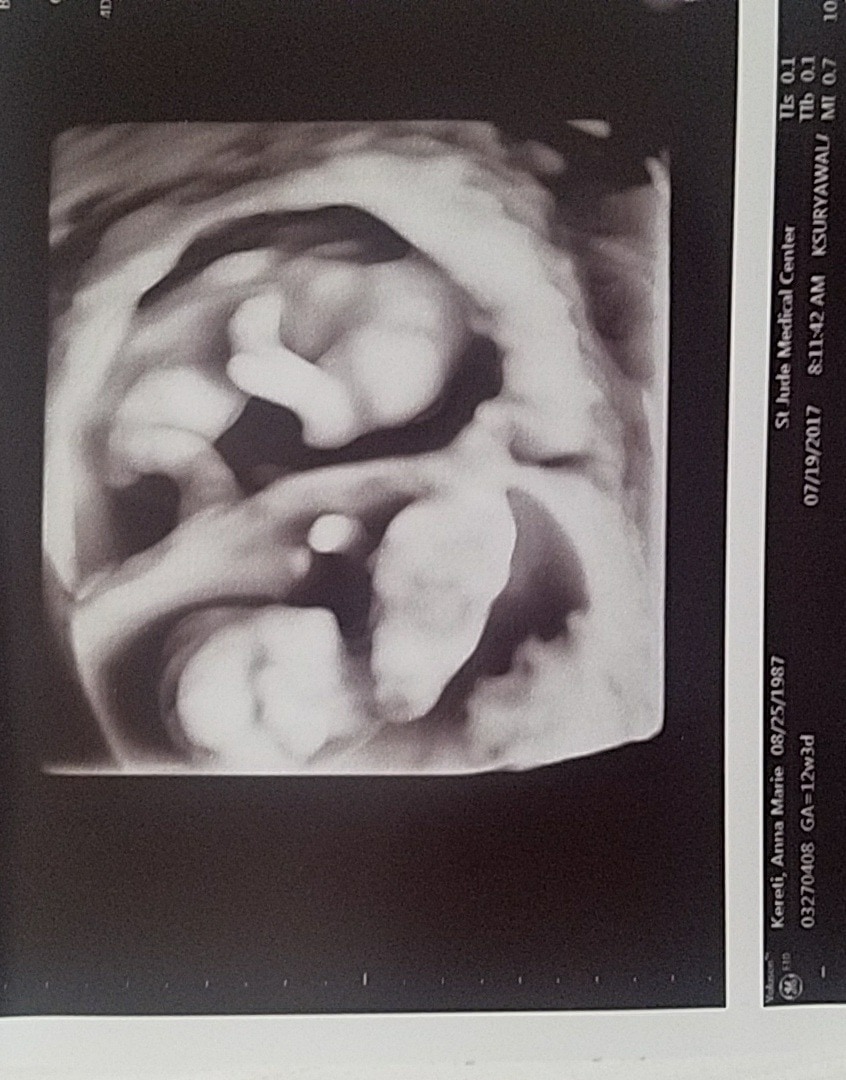

Ultrasound Photos at 12 Weeks Pregnant With Twins